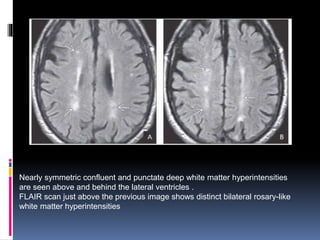

Nearly symmetric confluent and punctate deep white matter hyperintensities

are seen above and behind the lateral ventricles .

FLAIR scan just above the previous image shows distinct bilateral rosary-like

white matter hyperintensities